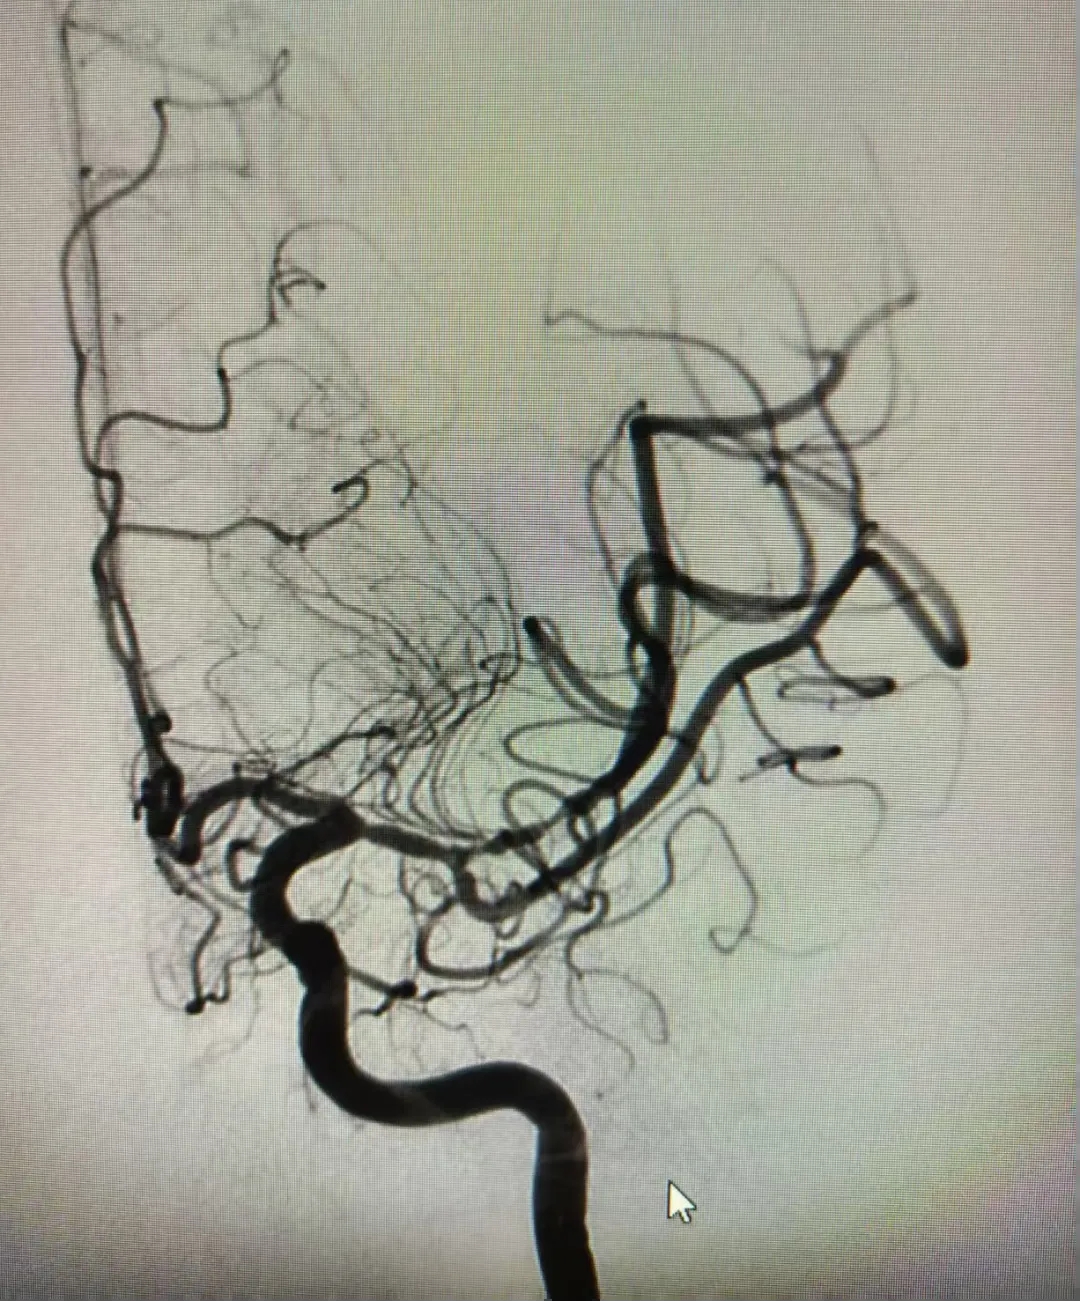

术中造影时发现,患者左侧大脑中动脉闭塞,随即进行了抽吸取栓术,患者血管成功打通,术中抽吸取出大负荷血栓。经过44分钟的紧张手术,血管完全再通,手术顺利完成。

术前

术后